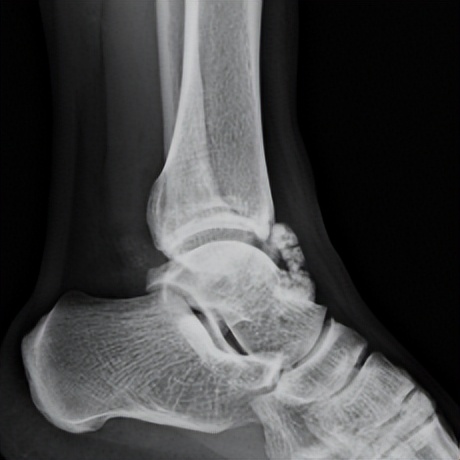

林先生来到省二医后,何河北医生为其进行了详细查体,检查后确诊为踝关节不稳+滑膜软骨瘤。

何河北制定了详细的手术方案,为患者开展踝关节镜下滑膜软骨瘤取出术+距腓前韧带重建术。他从患者踝关节中取出32颗“珍珠”(关节游离体),然后进行踝关节外侧韧带重建。

▲术前可见踝关节前方有大量“珍珠”。